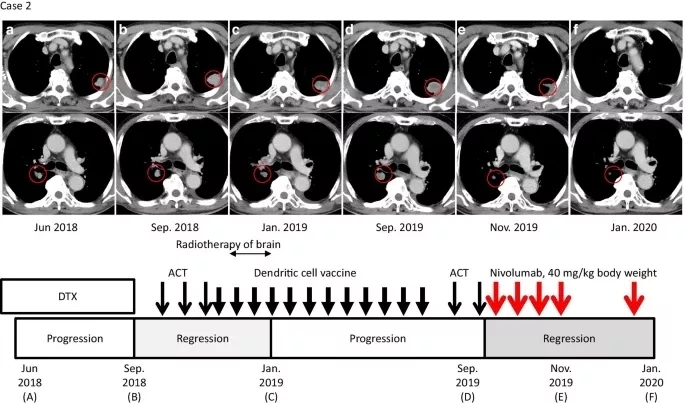

图2. 病例2临床病程

与治疗和疾病状态时间线相对应的轴位CT图像。红色圆圈表示肺和肺门转移性病变。a. (上)多西他赛(DTX)给药期间的状态。b. 过继细胞疗法(ACT)治疗前肺转移进展情况。c. ACT和树突状细胞(DC)疫苗治疗后肺转移的消退。d. 服用纳武利尤单抗前肺和肺门淋巴结转移的进展。e. 免疫检查点抑制剂(ICI)与ACT联合治疗8周后肺转移消退。在使用ICI维持治疗期间,缓解是持续的(f)。窄的黑色箭头、粗体黑色箭头和红色箭头分别表示ACT、DC疫苗和纳武利尤单抗给药(下)。

日本男性患者,于2016年6月被诊断为食管癌,时年77岁。CT和活检标本显示食管鳞癌临床Ⅳ期(UICC, T4N2M1)。于2017年7~11月接受氟尿嘧啶/铂的CCRT。2017年12月,胃镜检查显示食管癌完全缓解。患者于2017年7月至11月接受氟嘧啶/铂CCRT。2017年12月,胃镜检查显示食管癌完全缓解。患者一直为无疾病状态,直到2018年4月,常规CT显示双侧肺和右肺门淋巴结多发转移(图2a)。2018年5~9月,患者接受多西他赛作为二线化疗,但发现其肺转移已进展(图2b)。

患者于2018年10月至作者医院接受ACT,随后以2~3周的间隔进行3次αβT淋巴细胞的ACT,直到2018年12月。2018年12月26日到2019年6月28日,患者共接受了12次(间隔2~3周)应用MUC1、MAGE3和survivin的树突状细胞(DCs)脉冲治疗(图2),MUC1、MAGE3和survivin均作为肿瘤抗原在其肿瘤细胞上表达。在ACT和脉冲DC治疗期间,2018年11月发生脑转移,接受了脑转移立体定向放疗。常规CT显示,多个肺和淋巴结的转移病灶缩小,根据2019年1月实体瘤反应评价标准(RECIST)1.1版评估为部分缓解(图2c)。此外,2019年4月脑转移病灶也有所减少。

2019年9月,随访CT显示肺和肺门淋巴结转移灶再生,患者开始每月接受一次ACT治疗(图2d)。免疫组化染色显示肿瘤中PD-L1表达水平为1%,MSI阴性(数据未显示)。ACT后,患者接受纳武利尤单抗治疗(剂量为0.6 mg/kg体重,4次,每隔2周一次)作为诱导治疗的一部分。

2019年11月27日(纳武利尤单抗启动后8周)的随访CT扫描显示部分缓解,肺部病灶及和肺门部淋巴结肿块减少60%(图2e)。患者继续接受每隔3周一次、剂量为40 mg/kg体重的纳武利尤单抗治疗作为维持治疗。在患者2019年的临床病程中,放射学证据显示病变持续改善,由于患者临床状态良好且存活,因此继续使用纳武利尤单抗维持治疗(图2f)。在联合治疗期间没有不良事件的证据。